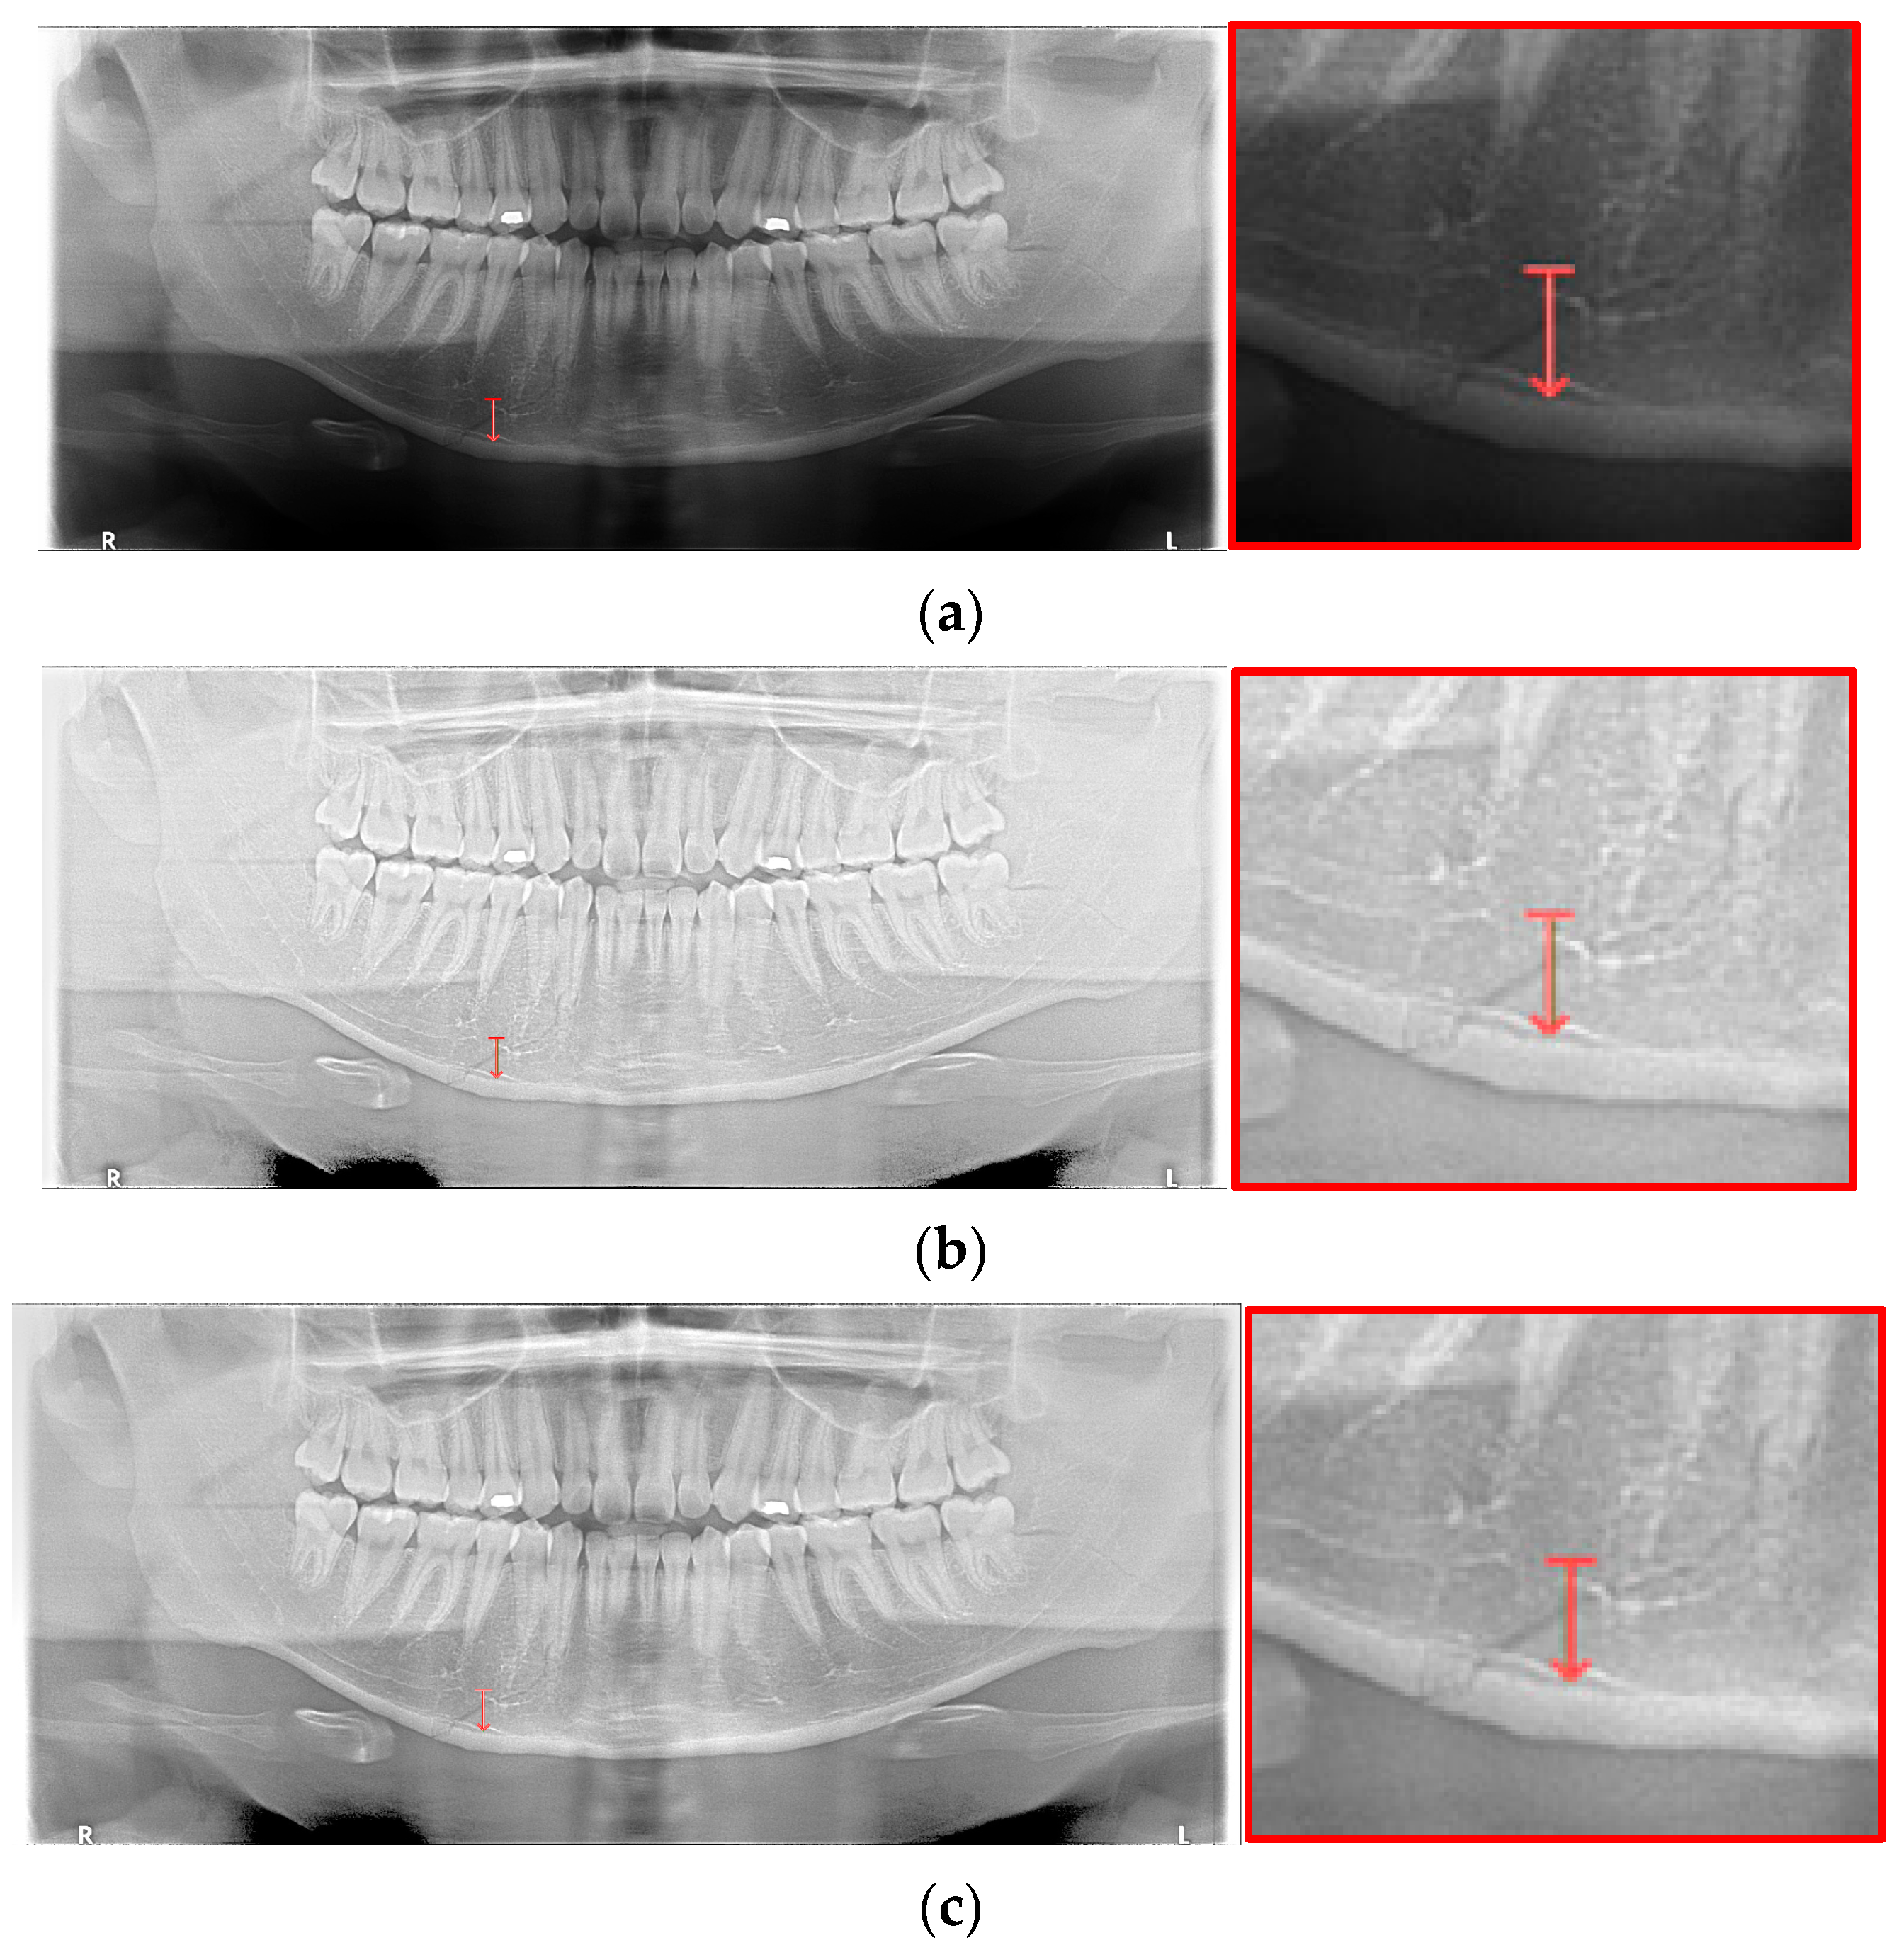

YOLO, Mask-R-CNN, and U-Net use different data-segmentation methods when constructing the training data. First, the mandibular fracture diagnosis module using Son et al.’s LAT YOLOv4 has a good diagnostic ability for fracture positions; however, it has a high undetected rate because it does not accurately distinguish fracture shapes and expresses fracture areas in the form of boxes. This module shows the diagnostic performance of precision of 97%, recall of 79%, and F1 score of 88%. In particular, fractures in the symphysis, body, angle, and ramus tend to be distributed in the middle of the mandible, and undiagnosed detection errors increase owing to irregular fracture shapes and overlapping location information. The advantage of location information is weakened; there is the possibility of a case where a fracture that is visible to the naked eye cannot be detected (Figure 3b). Therefore, additional applications such as Mask R-CNN, which is another object detection deep learning, and U-Net, which is used for medical image region segmentation, are needed to improve detection capabilities, especially recall scores representing undiagnosed performance in existing studies.

Figure 3.

The result of mandibular fracture detection: (a) diagnosis by oral and maxillofacial radiologist, (b) by LAT YOLOv4 module (with red boxes), (c) by Mask R-CNN (with colored polygons and boxes), and (d) by U-Net.

Unlike YOLO learning data consisting only of box coordinates and class information, Mask R-CNN requires the designation of a polygon-type learning region in the fracture region for the construction of a mandibular fracture learning dataset. However, in the case of shear fractures without gaps or dislocation fractures occurring in the condyle region, it was difficult to express the training data region using Mask R-CNN. Because these specific fracture regions cannot be drawn in closed polygon form, fracture regions are represented and trained in a box or simple form, such as YOLO learning data. In this case, for comparison with the results of the LAT YOLOv4 module [], training was performed with the same class structure on the same training data, and the detection results in the same test data were 57% precision, 70% recall, and 63% F1 scores. The fracture shape of the condyle region is not properly expressed, which leads to an error in judgment owing to the fracture shape, and the error detection between teeth is also recognized as a fracture in the panoramic image, resulting in a lower precision score (Figure 3c).

For U-Net training, a training dataset labeled according to the shape of the fracture is constructed. This makes it easy to generate U-Net training datasets of fracture sites with complex spacing. However, shear fractures or displaced fractures are difficult to be labeled. Therefore, in the case of shear fractures, the parts which are visible even with solid and crack lines in the shear fractures were labeled as much as possible. But the displaced fractures were not labeled because it adversely affected the fracture detection accuracy during U-Net training. Additionally, when segmentation and labeling are performed differently from complex fracture shapes, it adversely affects the training process and reduces mandibular fracture detection performance. Figure 3d confirms that U-Net shows good segmentation performance for general fracture types but U-Net shows poor segmentation performance for dislocated fractures in the condyle region because U-Net was not trained in condyle region. Therefore, U-Net is advantageous for learning the rest of the fracture areas except for some of the severe shear and displaced fractures.